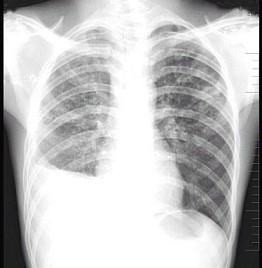

问题 男性患者,20岁,胸闷、低热1个月余,突然咯血,X线检查如图,最合理的诊断是 ( )

选项 A.肺结核(Ⅰ型)伴右侧胸腔积液 B.肺结核(Ⅲ型)伴右侧胸腔积液 C.肺结核(Ⅱ型)伴右侧肺不张 D.肺结核(Ⅲ型)伴右侧肺不张 E.肺癌

答案 B